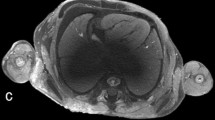

All examined publications reported successful scanning of human fetuses with a preclinical UHF-MRI scanner (see Table 2) with a field strength from 7 to 11.7 T. Though the bore diameter of most scanners is between the 16 and 30 cm, the use of a radiofrequency (RF) coil limits the inner diameter of the scanning plane to typically less than 10–20 cm, which hampers scanning whole fetuses > 20 weeks of gestation with these preclinical scanners. Several authors examined the added value of UHF-MRI over low-field MRI [14, 15, 37], as demonstrated in Fig. 5 by Thayyil et al (2009) [14]. They conclude, that UHF-MRI enables scanning on much higher resolution resulting in greater diagnostic usefulness, especially in fetuses below 16 weeks of gestation [14, 15, 37].

UHF-MRI and low-field MRI images of the same fetus. a Coronal, (b) sagittal, and (c) axial images obtained with three-dimensional T2-weighted MRI at 9.4 T. d Coronal, (e) sagittal, and (f) axial images obtained with three-dimensional T2-weighted MRI at 1.5 T. Figure adapted from Post-mortem examination of human fetuses: a comparison of whole-body high-field MRI at 9.4 T with conventional MRI and invasive autopsy (Thayyil et al. 2019) [14] with permission form Elsevier